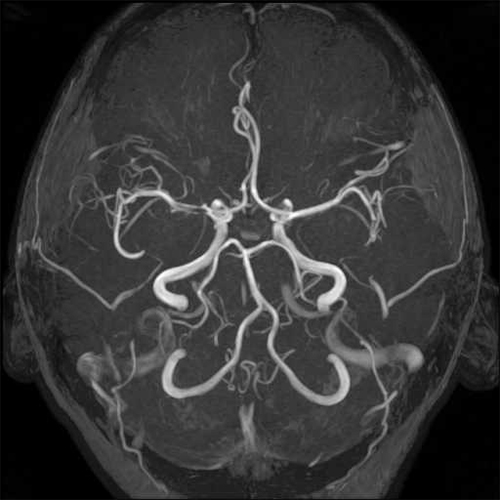

- Αγγειοχειρουργική